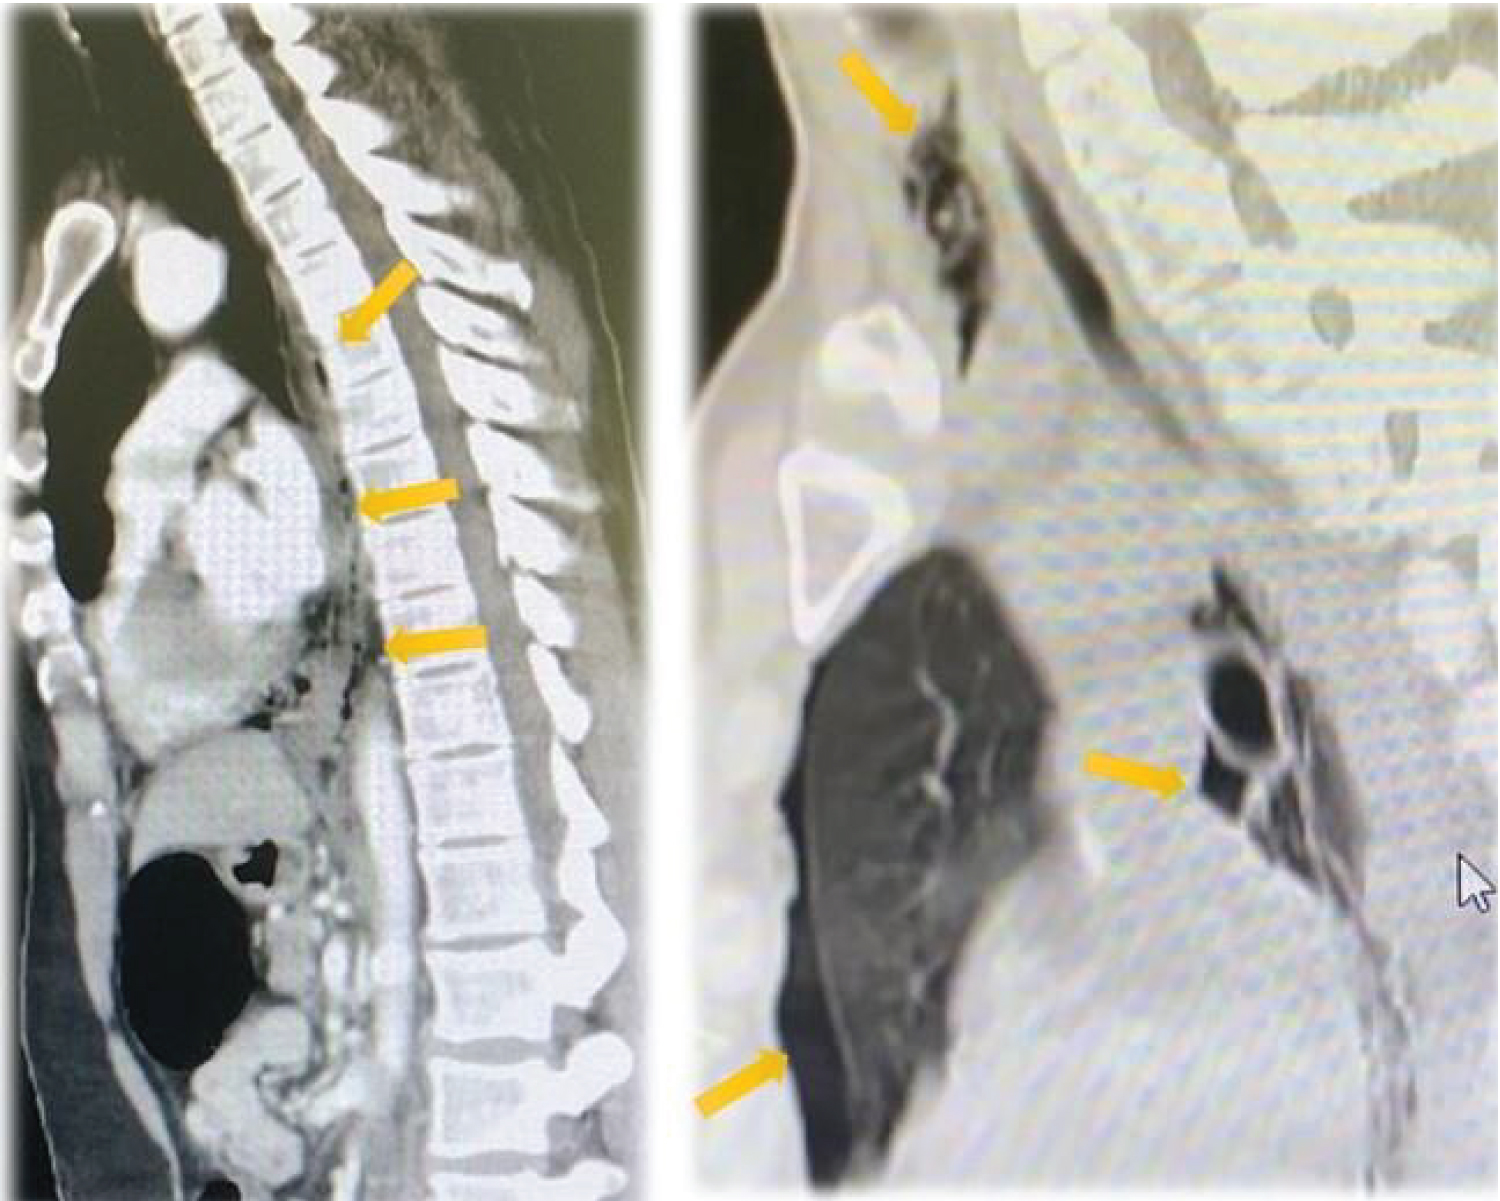

A male ages 40-50 years-old presented to the emergency department with chest pain with radiation for upper abdominal and left flank. As a personal history, of anxiety, in treatment with diazepam and duloxetine. There is no previous relevant history of gastrointestinal disease, and he did not have any preexisting disease and allergic history. His symptoms began suddenly after vomiting and he complained an intense pain (the pain score was 9 out of 10 based on the verbal rating scale). He also reported nausea, diaphoresis, and had no symptoms of severe acute respiratory syndrome. On admission, physical examination showed pale and sweaty skin, his initial vital signs were a blood pressure of 112/73 mmHg, heart rate of 135 beats per minute, respiratory rate of 25 breaths per minute, temperature of 36.2 °C, oxygen saturation 98% on room air. During the initial clinical examination, he was pale and sweaty and very complaining in the retrosternal and left lumbar region. Apart from the above signs, he had no other remarkable findings on systemic examination. A metabolic acidosis with high anion gap (pH 7.37, pCO 2 29 mmHg, pO 2 102 mmHg, bicarbonate 16.8 mmol/L, saturation 98.7%, anion gap of 14 mEq/L, lactate 1.4 mmol/L) was present on his initial blood gas. The initial chest X-ray showed no acute abnormalities Figure 1, most notably no pneumothorax or pneumomediastinum and 12-lead electrocardiogram showed a normal sinus rhythm. The patient's laboratory studies revealed a mild leukocytosis (14 10^3/uL) and C-reactive protein was below 1 mg/L. His renal and electrolyte profile was normal (creatinine of 1.5 mg/dl). There was no abnormal finding by the levels of cardiac biomarkers, pancreatic lipase and amylase, or D-dimer. To clarify the clinical case, a CT was performed, which showed left pneumothorax, anterior pneumomediastinum and indistinct esophageal wall with pneumomediastinum at just above the gastro-oesophageal junction, suggestive of esophageal rupture Figure 2 and Figure 3. General surgery was consulted and due to history of the present illness two sets of blood culture were collected and broad-spectrum antibiotics and antifungals with piperacillin/tazobactam and fluconazole were initiated, as well as analgesia and prokinetics. Faced with the diagnosis of with esophageal rupture, the patient was transferred to a referral center and submitted to surgical repair with placement of an esophageal prosthesis with clinical improvement. He was discharged home on the 12 th postoperative day. After one month’s follow-up consultation, the patient is well with no impairments.

Figure 2: Axial view of CT chest with evidence of left pneumothorax and pneumomediastinum (yellow arrows). View Figure 2

Figure 3: Sagittal view of CT chest showed extra-luminal free air in the mediastinum (yellow arrows) and left-sided pneumothorax. View Figure 3